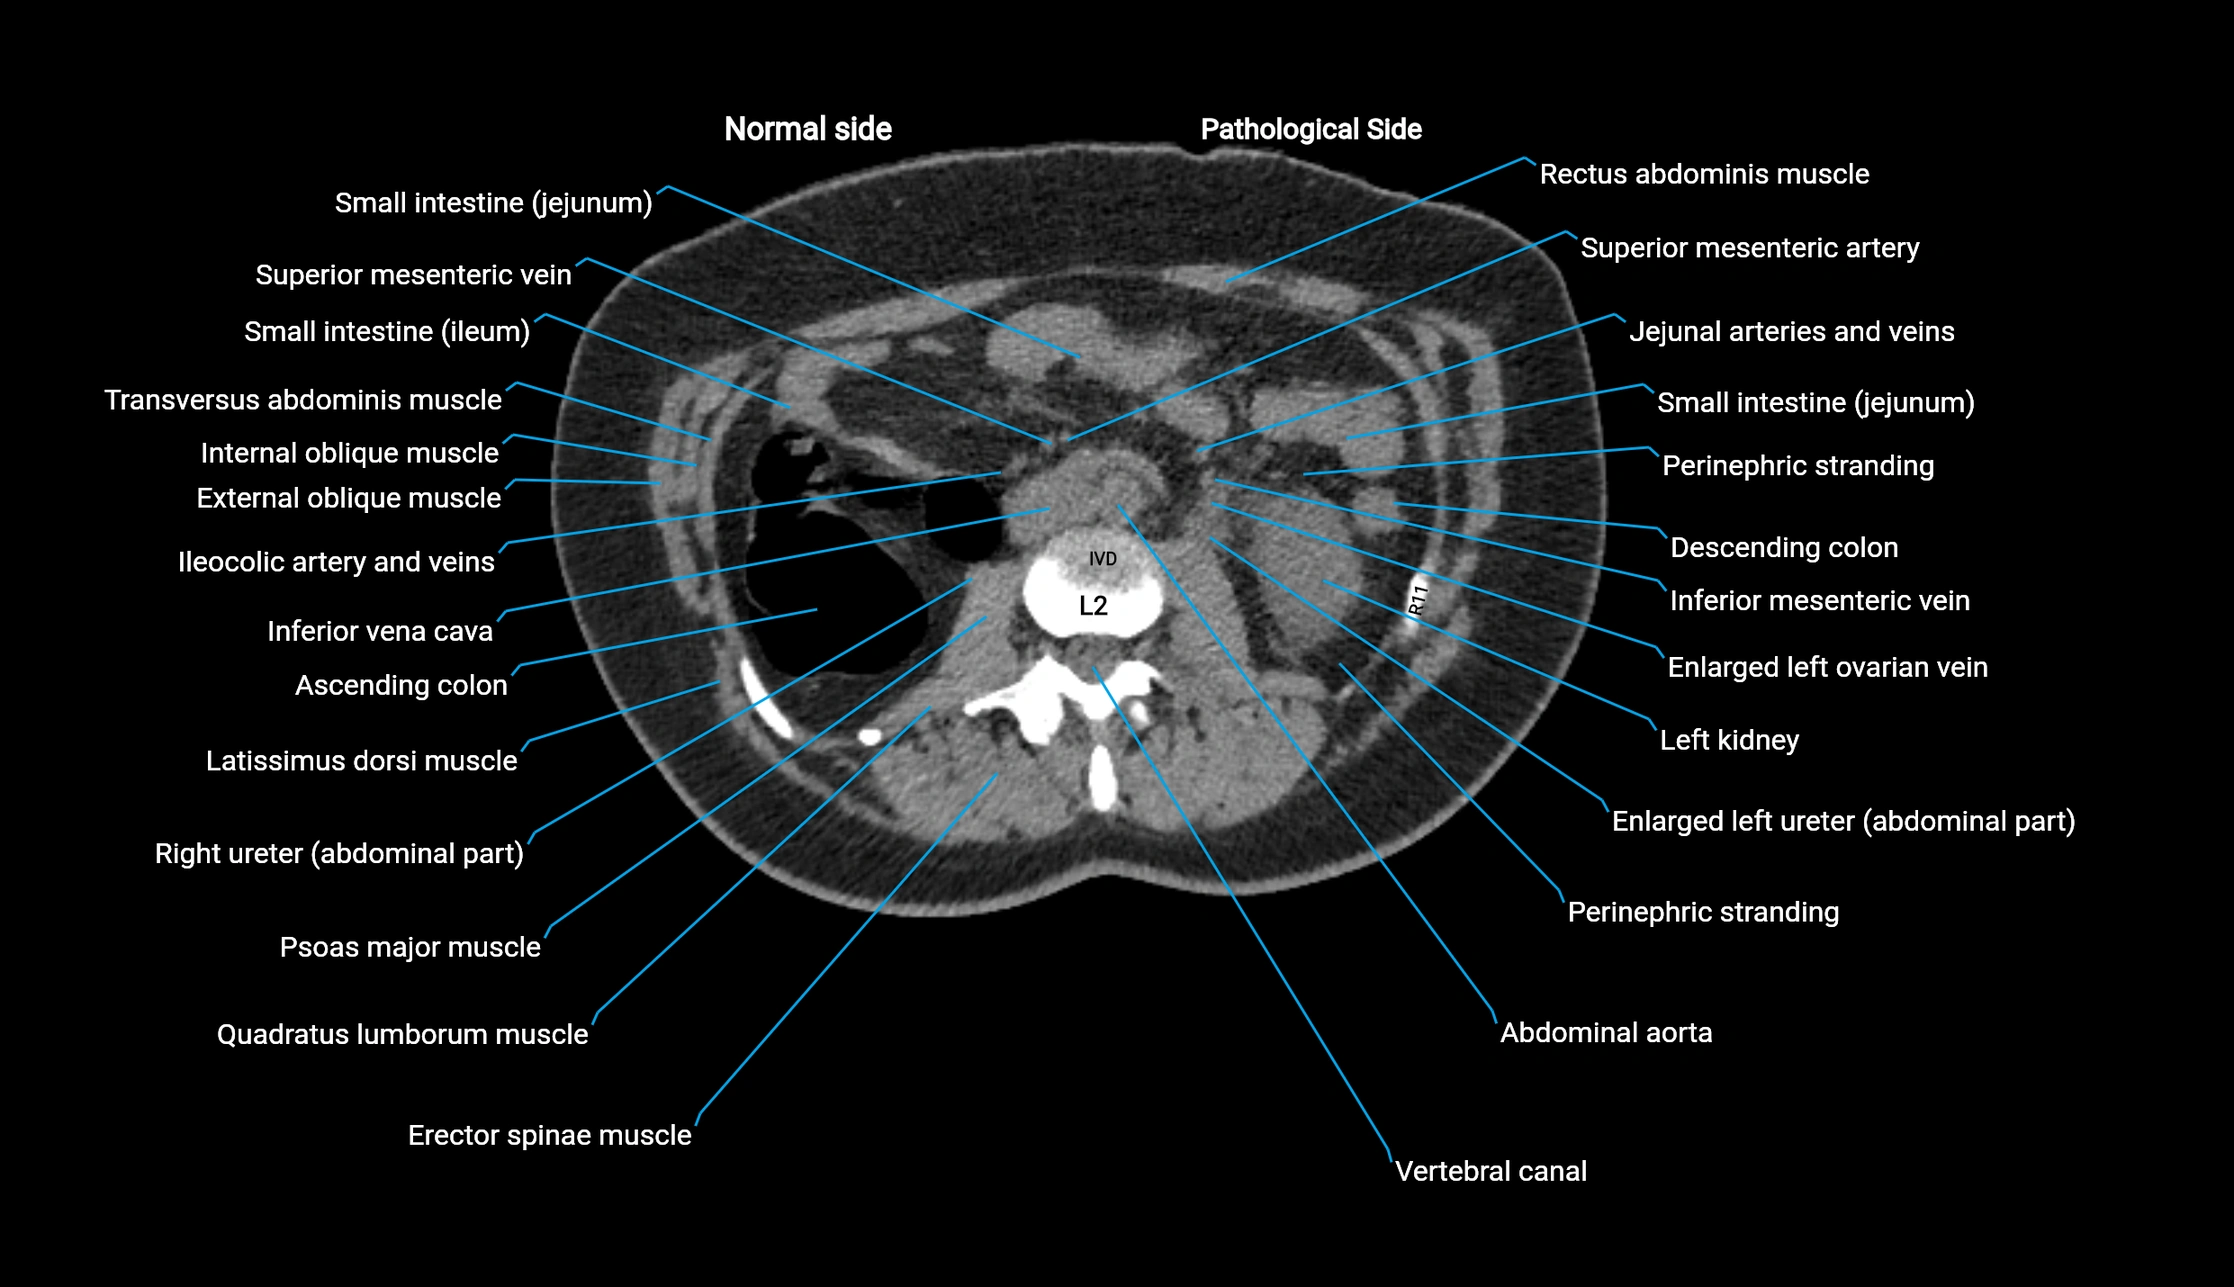

CT Appearance

Non-contrast CT:

• Demonstrates cortical bone of acetabular rim in excellent detail

• Detects fractures, dysplasia, retroversion, or bony overcoverage (pincer impingement)

• 3D reconstructions used in preoperative hip surgery planning